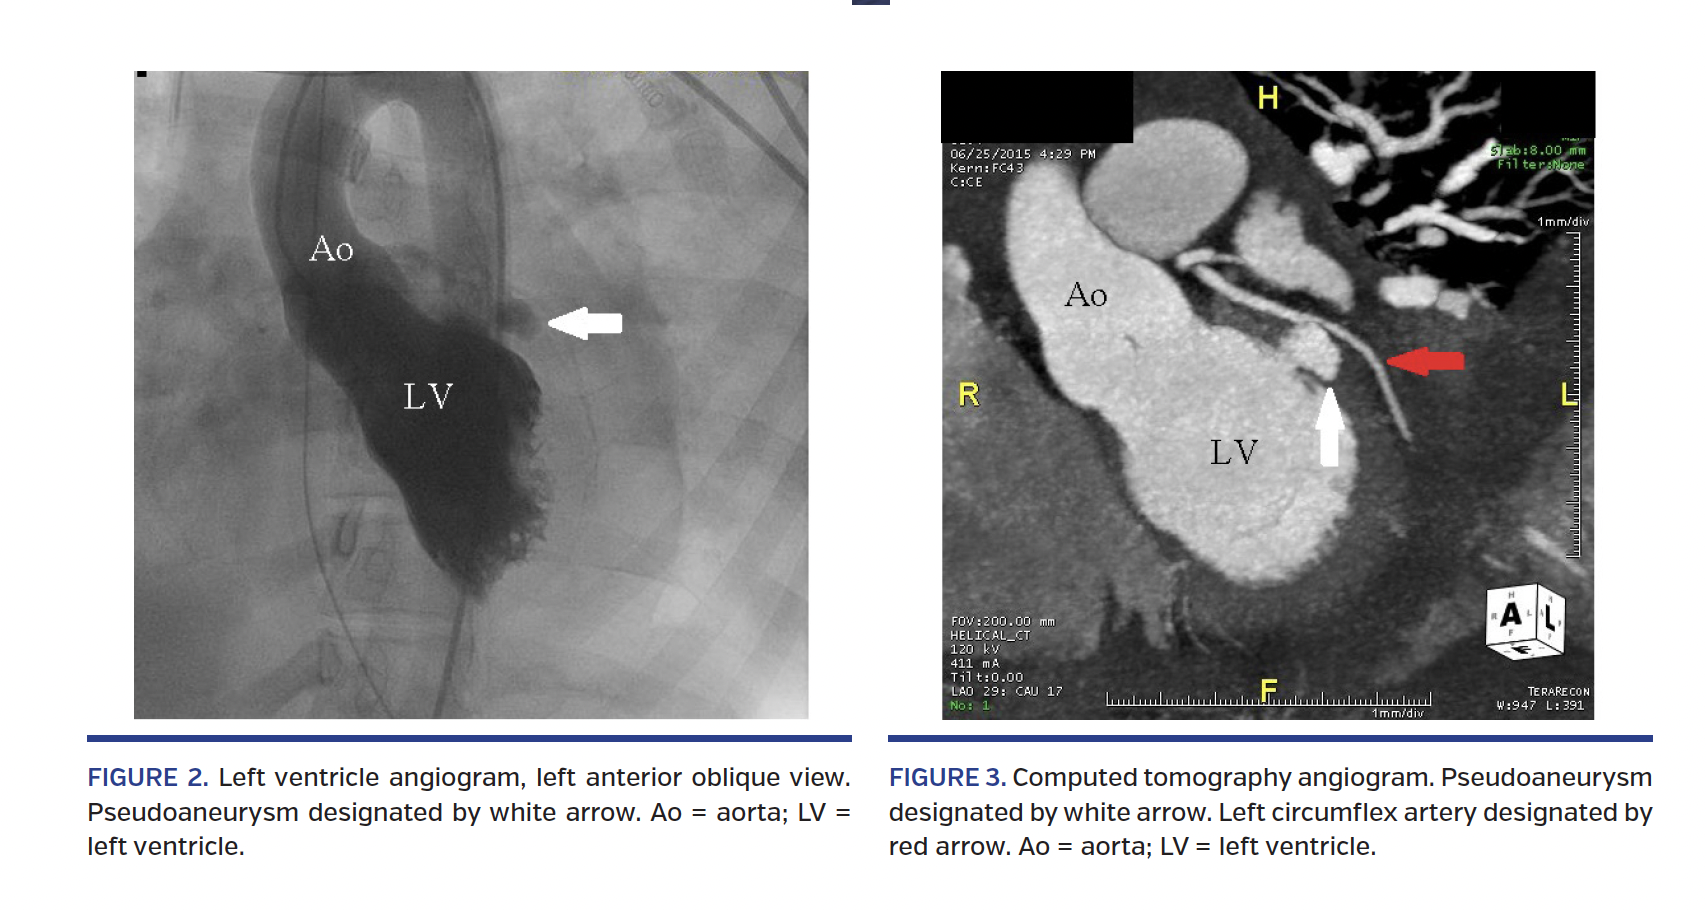

On hospital day 5, the patient developed hypotension requiring vasopressors. A repeat TTE revealed a moderate pericardial effusion and increased MR with an unusual eccentric jet. Subsequent transesophageal echocardiogram demonstrated a possible pseudoaneurysm at the base of the posterior leaflet of the mitral valve with new moderate MR (Figure 1). She underwent left and right heart catheterization with hemodynamic data consistent with pericardial tamponade. Left ventricular angiogram showed a possible pseudoaneurysm at the base of the anterolateral wall (Figure 2; Video 1). Pericardiocentesis was performed, revealing 300 mL of dark sanguineous fluid and resulting in hemodynamic improvement. Subsequent cardiac computed tomography angiogram demonstrated 13 mm pseudoaneurysm of the posterolateral wall just below the mitral annulus, with a 5 mm neck (Figure 3).